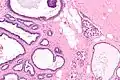

Collagenous spherulosis is characterized by a tubular/cribriform architecture with intratubular eosinophilic material that classically is arranged like the spokes of a wheel ("radial spikes"). There is usually no mitotic activity, and two cells populations (epithelial & myoepithelial) are present, like in benign breast glands.

The lesions are typically small (less than 50 spherules per lesion, less than 100 micrometers in size) and may be multifocal.

High mag.